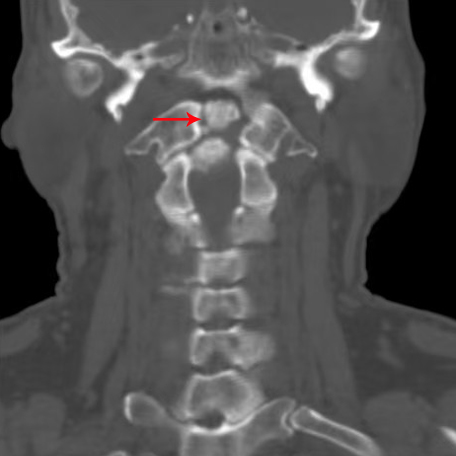

60多岁的田先生三个月前因颈痛伴四肢麻木数月来到潞河医院神经内科和脊柱外科门诊就诊。田先生曾出现摔伤后呼吸心跳骤停,当时经及时抢救得以转危为安。此次就诊,田先生及家人想寻找并拆除引起摔倒后呼吸心跳停止的“定时炸弹”。进修归来的赵鹏医生根据病史、查体、影像学检查,明确诊断:“寰枢椎不稳定(图1齿状突游离小骨)”;2.高位颈脊髓损伤(图2MRI:颈脊髓明显的水肿信号)。为了保证手术安全,赵鹏医生与已开展寰枢椎手术工作的他院专家反复讨论,并结合医院现有设备条件,从手术体位、头架使用、机器人导航操作等细节进行模拟演练,以确保手术操作按预定方案顺利进行。

箭头所示为齿状突游离小骨